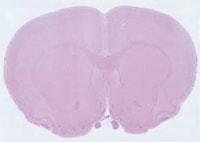

Transmitted lighting is typically used for two different types of samples: objects that are transparent or semi-transparent or those that are opaque and require backlighting for measurement. For this type of setup, light shines from behind the object, passes through it, and is received by the eyes or a camera. This lighting is mainly used for biological applications where users are imaging cells or tissues on glass slides or other specimen holders. It also works well when backlighting an object, which creates a well-defined silhouette of its profile, allowing for more precise and accurate measurements.

Transmitted lighting comes standard with the motorised XY stage, producing consistent brightness from low to high magnifications. It is also possible to use the LED transmitted lighting in conjunction with reflected illumination from the lens. The light from each source can be adjusted independently, making it possible to perform observation with an optimum balance of light intensity.

When viewing a sample at low magnification, the light is applied uniformly to the entire target. As the magnification is increased, the light can be concentrated to improve the contrast of the image.